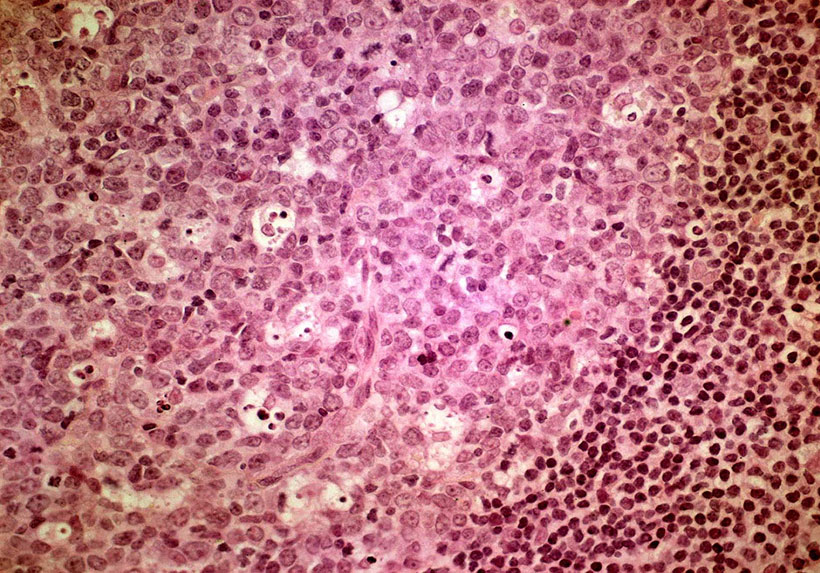

Изображения и схемы: как выглядит лимфа